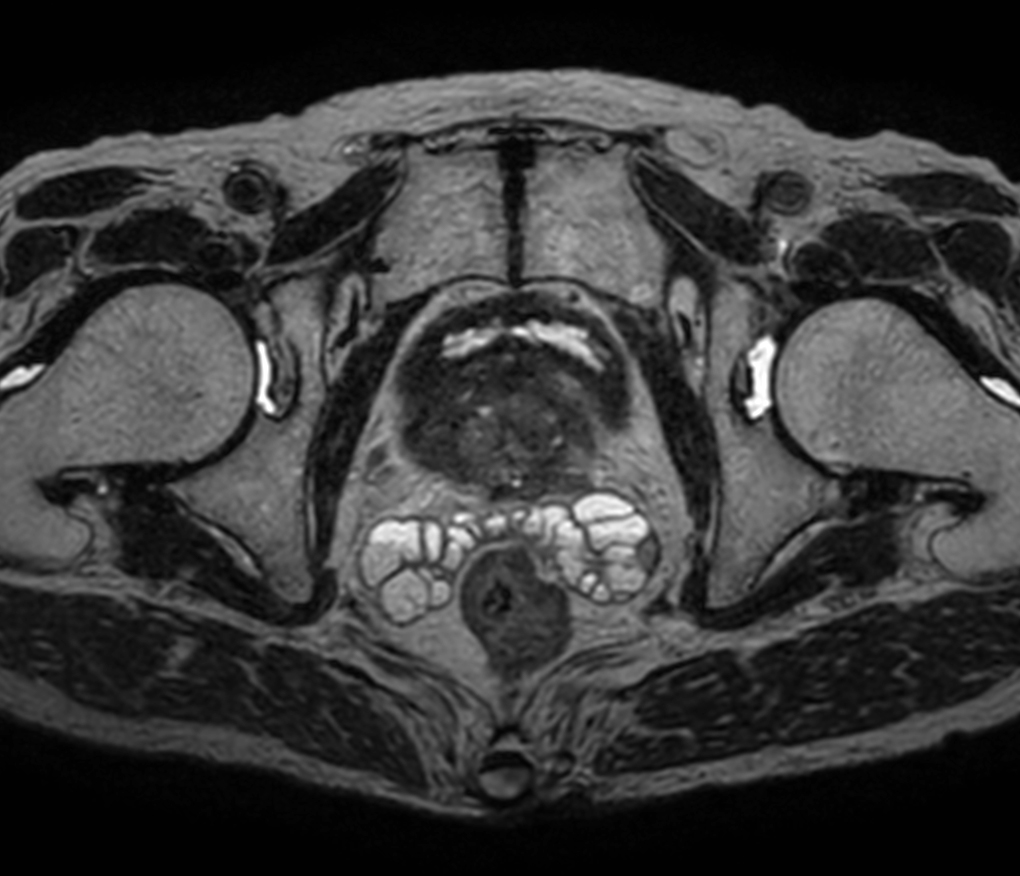

Axial T1w TSE